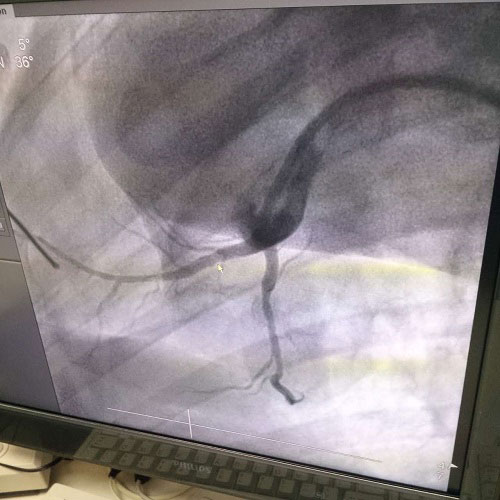

生物全降解鎂合金藥物洗脫支架是我由公司自主立項研發(fā)、主要工藝技術(shù)完全自主,具有完全自主知識產(chǎn)權(quán)。并且可行性強(qiáng),前期研發(fā)基礎(chǔ)扎實(shí),市場需求迫切,實(shí)施風(fēng)險可控,屬全球同行業(yè)領(lǐng)先技術(shù),填補(bǔ)國內(nèi)技術(shù)發(fā)展空白,符合國家產(chǎn)業(yè)發(fā)展政策,社會、經(jīng)濟(jì)效益巨大。目前鎂合金藥物支架已進(jìn)入動物實(shí)驗階段,植入動物體內(nèi)一個月之后效果良好。